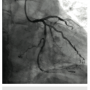

A 4 French (Fr) Glidesheath (Terumo Corporation) was inserted in the right radial artery and a vasodilator cocktail of 2.5 mg verapamil and 100 micrograms of nitroglycerin were given via the sheath. Since this was to be a planned chronic total occlusion (CTO) intervention, 5,000 units of heparin were given via an intravenous route. The 4 Fr introducer was exchanged out for a 6.5 PB4.0 Asahi sheathless guide (Asahi Intecc) (Figures 1-2). A control angiogram of the left coronary (Figure 3) reveals a total occlusion in the distal circumflex artery.

A Pilot 200 wire (Abbott Vascular) was loaded in a CrossBoss catheter (Boston Scientific) and advanced into the circumflex artery. The CrossBoss was slowly advanced, using the Pilot wire to redirect the device to remain as close to the lumen as possible. Once past the total obstruction, the Pilot 200 wire was used to re-enter the distal circumflex (Figures 3-4). A balloon dilation with a 1.5 mm x 20 mm long balloon was performed at 12 atmospheres (atm) followed by a 2.5 mm x 20mm balloon at 12 atm. A Runthrough wire (Terumo) was placed in the first marginal and stenting of the circumflex was performed using a 2.5 mm x 38 mm Promus Premier stent (Boston Scientific) overlapped with a 3.0 mm x 24 mm Promus Premier stent. High-pressure inflation in the entire stented segment was performed using a 3.0 mm balloon. The segment proximal to the first obtuse marginal was dilated to high pressure using a 3.25 mm balloon (Figures 5-7). A good angiographic result was seen (Figure 8).